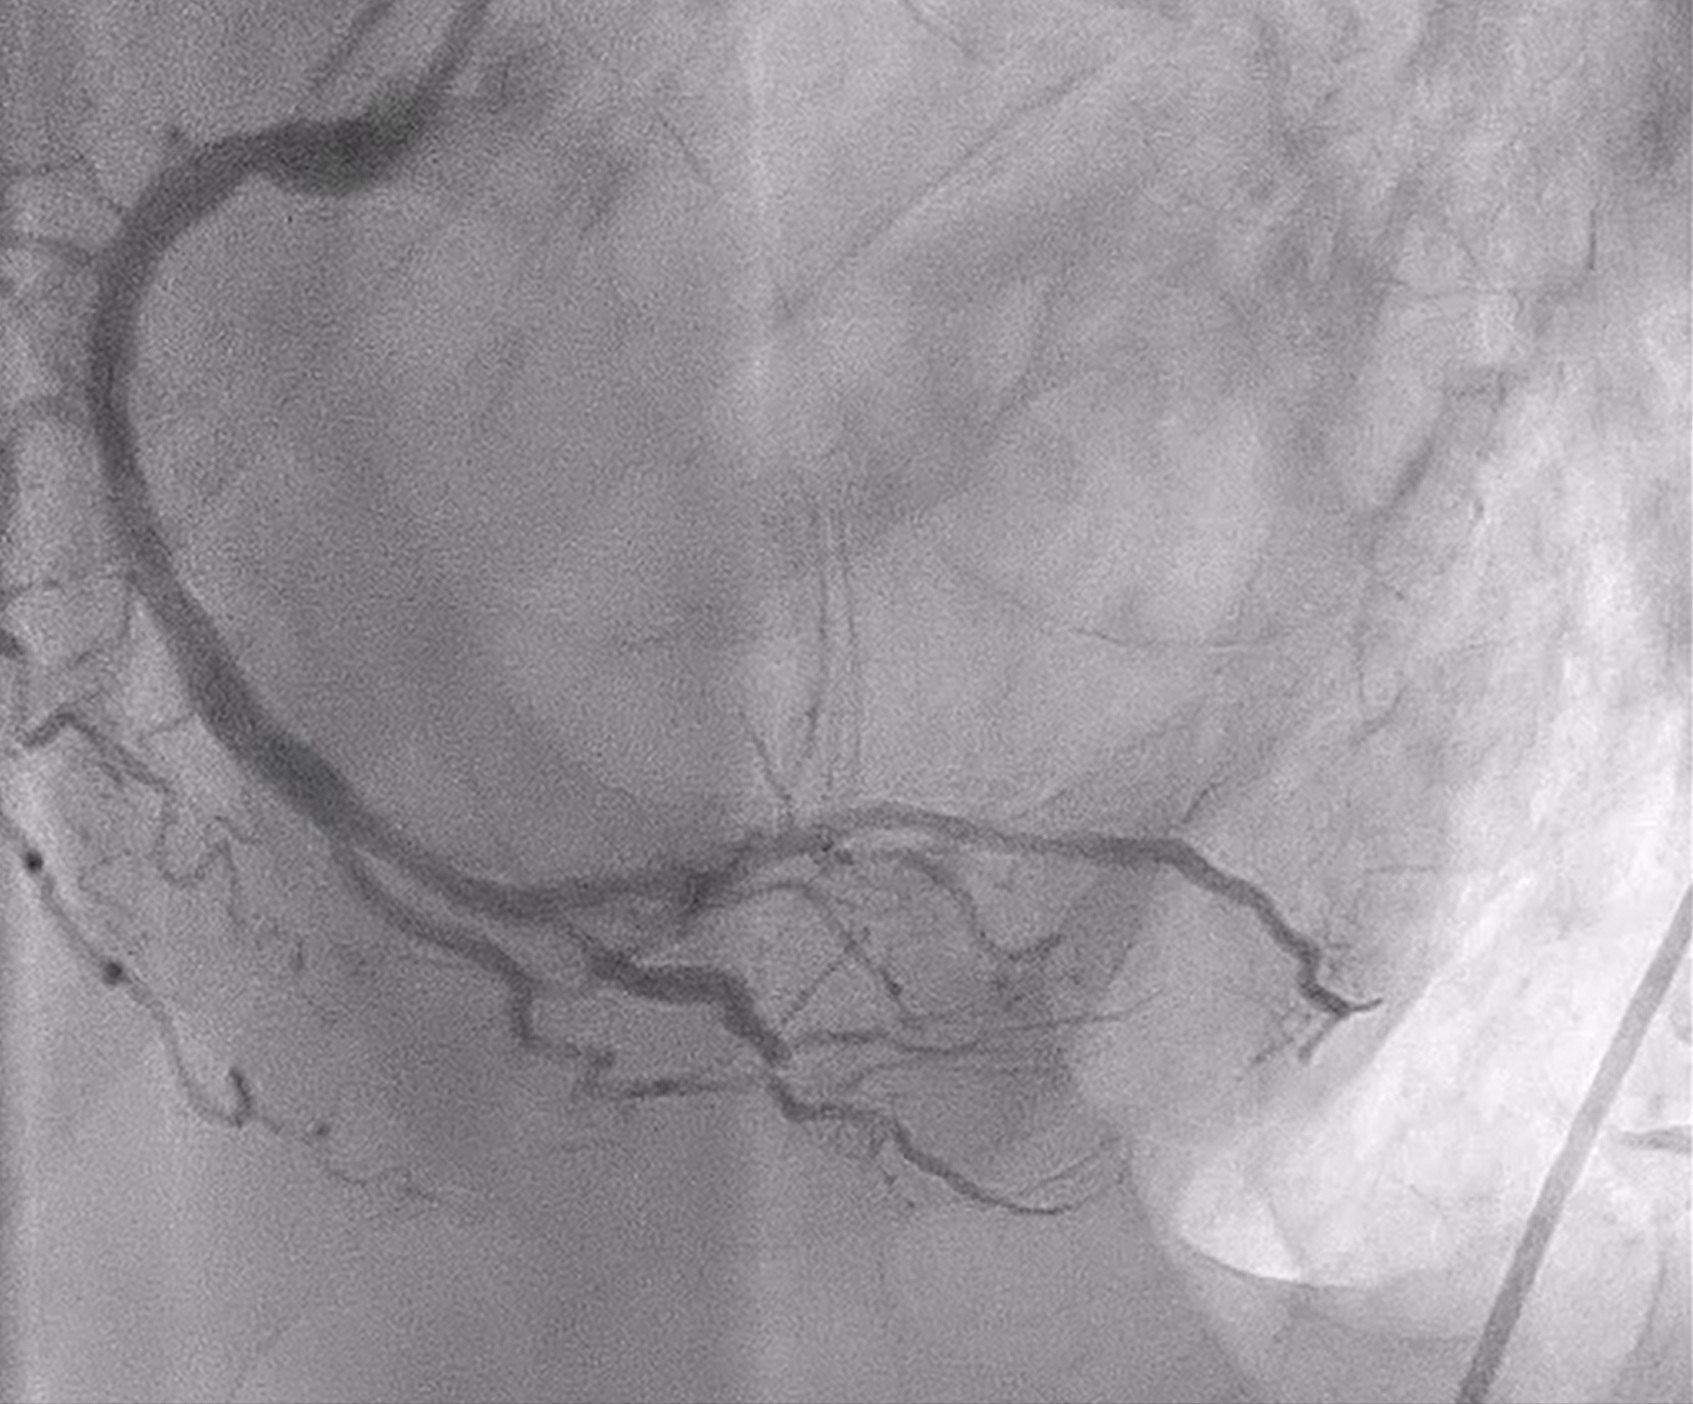

Coronary angiography revealed heavily calcified along LM, proximal to mid LAD, LCx and proximal RCA. 50% stenosis at distal LM bifurcation (Medina 1-1-0). 70% stenosis at proximal LAD and total occlusion at mid LAD. Total occlusion at proximal LCx. No significant stenosis of RCA. There were collateral circulations from septal branch of LAD to distal LAD and from PL to distal LAD and distal LCx.

We performed PCI at CTO LAD and LCx with contralateral injection with antegrade wiring and upfront rotablation at LM, LAD and LCx due to heavily calcified lesion. The 7 Fr EBU 3.5 and 6 Fr JR 4.0 catheter were engaged into LCA and RCA, respectively. We opened the LCx CTO segment using microcatheter with Fielder XT guidewire (GW) then rewire from LCx to distal LAD. The CTO GW was exchange to RotaWire Floppy. Rotablation was done at LM-mid LAD with Burr 1.5 mm and LM-proximal LCx with Burr 1.5 mm. IVUS showed EEL of mid LAD = 2.5 mm, proximal LAD = 4.0 mm, distal LM = 5.5 mm and proximal LCx = 3.5 mm. The lesion of mid LAD was prepared with scoring balloon 2.0/15 mm and LM-proximal LAD with scoring balloon 3.5/15 mm. A 2.5/33 mm stent was deployed from proximal-mid LAD. We decided to stenting the lesion at proximal LCx before stenting the lesion at LM-proximal LAD using provisional one stent and POT-kiss-POT technique. A 3.0/26 mm stent was deployed at proximal LCx. A 3.5/38 mm stent was deployed from distal LM-proximal LAD and 3.5/13 mm stent from ostial LM-distal LM. POT was done with a non-compliance (NC) 5.0/12 mm balloon along LM stent. Kissing balloon inflation with NC 3.0/15 mm balloon at LM-LCx and 3.5/15 mm balloon at LM-LAD then final POT with NC 5.0/12 mm was done. IVUS showed well stent expansion, no malapposition and no stent edge dissection. The patient had no re-admission. Echocardiography after 3 months showed significant improvement of LV function to 56%.